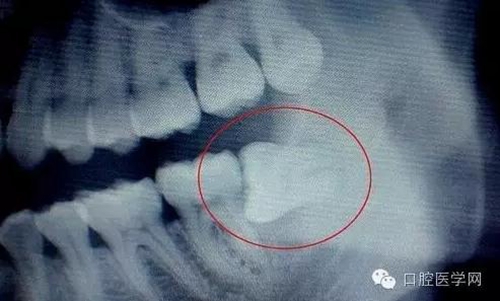

牙齒萌出困難稱為"阻生齒"或"埋伏牙"。阻生齒最常見于下頜第三磨牙,此牙萌出年齡在20歲左右,故稱為"阻生智齒"。阻生智齒會產(chǎn)生下列危害:

(1)冠周炎:智齒因阻生而使牙冠不能完全外露,牙冠周圍的牙齦成袋狀,極易積存食物、滋養(yǎng)細(xì)菌。當(dāng)全身抵抗力下降時引起急性冠周炎。